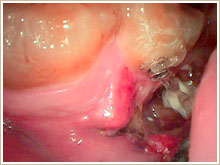

割れた歯を抜歯し、きれいにします。

![]()

歯専用の接着剤で歯をつなぎ合わせ、PRPを歯に塗布しています。

歯を元に戻して1ヶ月で再生します。